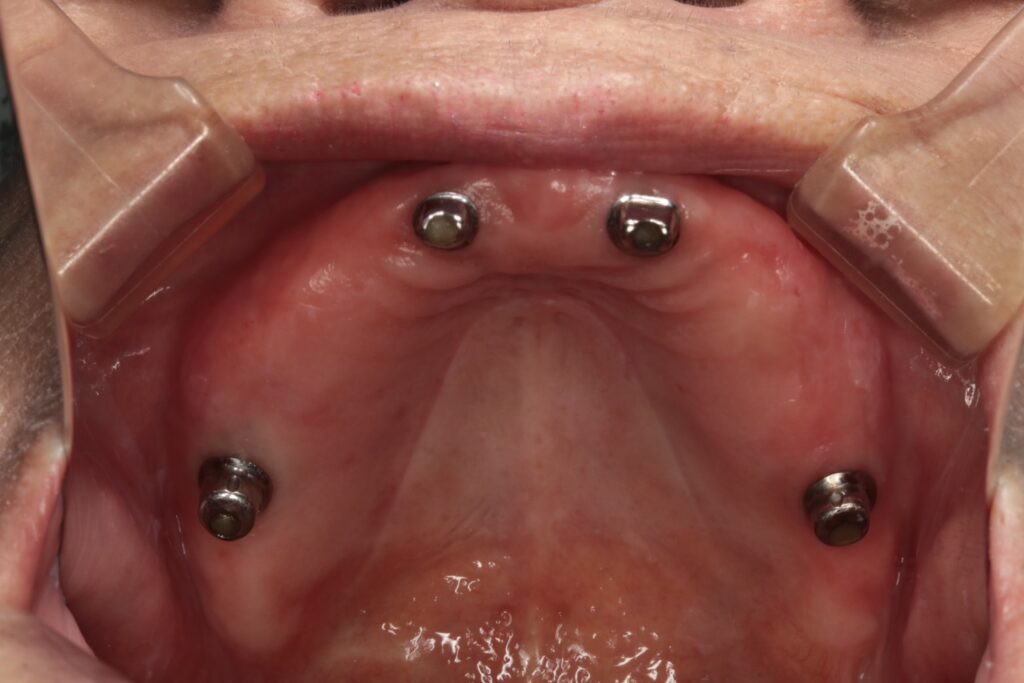

その後、上顎に2本のインプラントを埋入しました。

過去にブリッジ治療が行われていた部分を撤去し、インプラント治療へ変更。

骨が不足していたため、骨移植(GBR)を併用しています。

1.欠損部位(上下顎)のインプラント治療

2.上顎をインプラントオーバーデンチャーへ変更

今回使用したのは、精密性が高いコーヌステンチャー(ロケーター義歯よりも精密)。